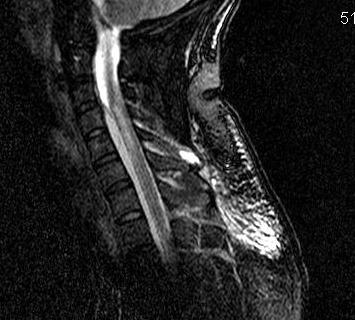

MRI

Investigation of choice

- T1: Low signal intensity mass

- T2: High signal intensity mass

- 85% sensitivity

Gadolinium enhancement T1

- peripherally or homogenous / typical of all abscess on MRI

- increases sensitivity to 95%

Assess levels

- multi level epidural pus

- need multilevel laminectomy and passage of catheter to aid washout

Also assess

- vertebral body osteomyelitis

- cord pathology

- other DDx (HNP, tumour, cord infarct)